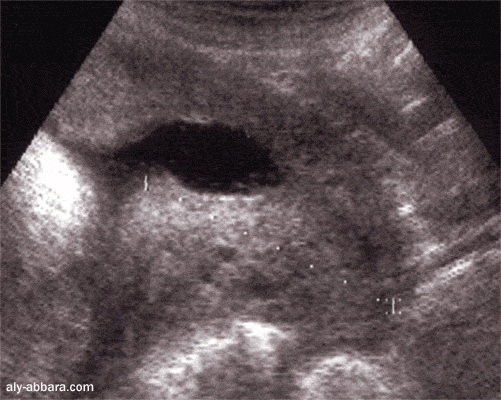

Coupe sagittale passant par le col utérin à 41 SA montrant l'aspect échographique de

l'anneau de constriction de la jonction entre le segment inférieur et le corps utérin

A ne pas confondre avec un col utérin long et une hernie de la poche des eaux dans le canal cervical